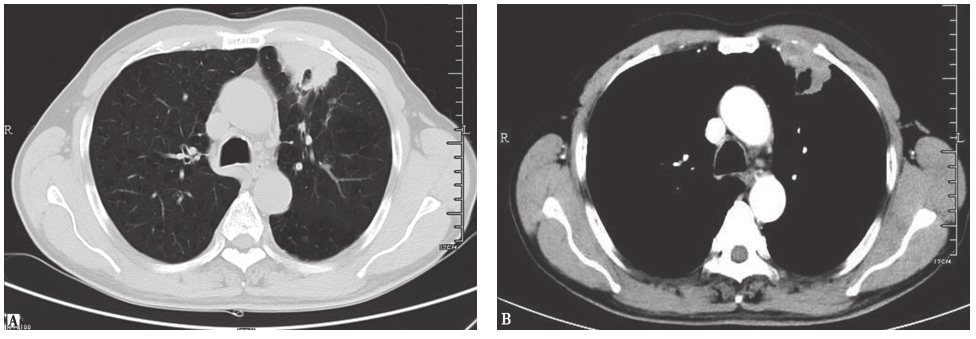

胸部CT:两肺野内可见多发结节状、斑片状密度增高影,以两上肺为主,病灶形态欠规整,其内密度不均,部分内见空洞(图1)。

图1入院前胸部CT表现